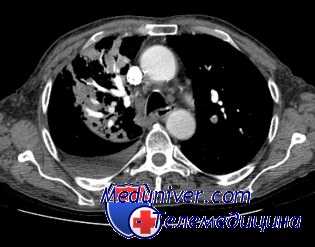

- КТ. Компьютерная томография выполняется в трех проекциях. Это позволяет получить точную информацию о размерах опухоли, распространенности опухолевого процесса, вовлечении в него средостения, плевры, регионарных лимфоузлов, диафрагмы, оценить степень поражения бронхов (стеноза, окклюзии).